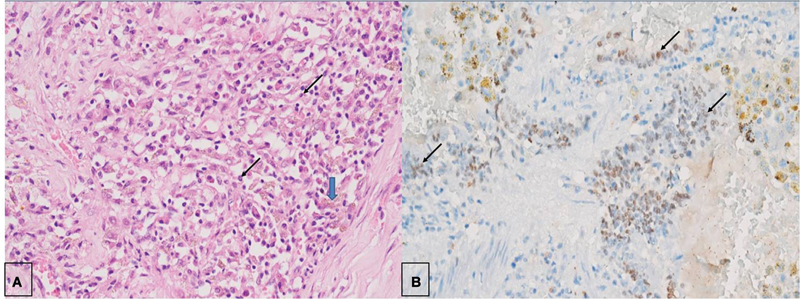

Pulmonary sclerosing pneumocytoma is a rare benign neoplasm typically seen in middle-aged women. The exact preoperative diagnosis is quite challenging considering its nonspecific clinical and radiologic features along with complex histology. Moreover, obtaining an exact histopathological diagnosis can be difficult especially with the small biopsy specimens. Most patients are generally asymptomatic with incidental detection of peripheral, homogenous, solitary pulmonary nodule. It is essential to differentiate it from other mimickers including malignant lesions as limited surgical resection is curative in these cases without adjuvant therapy. We present a rare giant cystic variant of pneumocytoma, in a young male, which was initially mimicking inflammatory myofibroblastic tumor even on preoperative histology.

Abstract Image